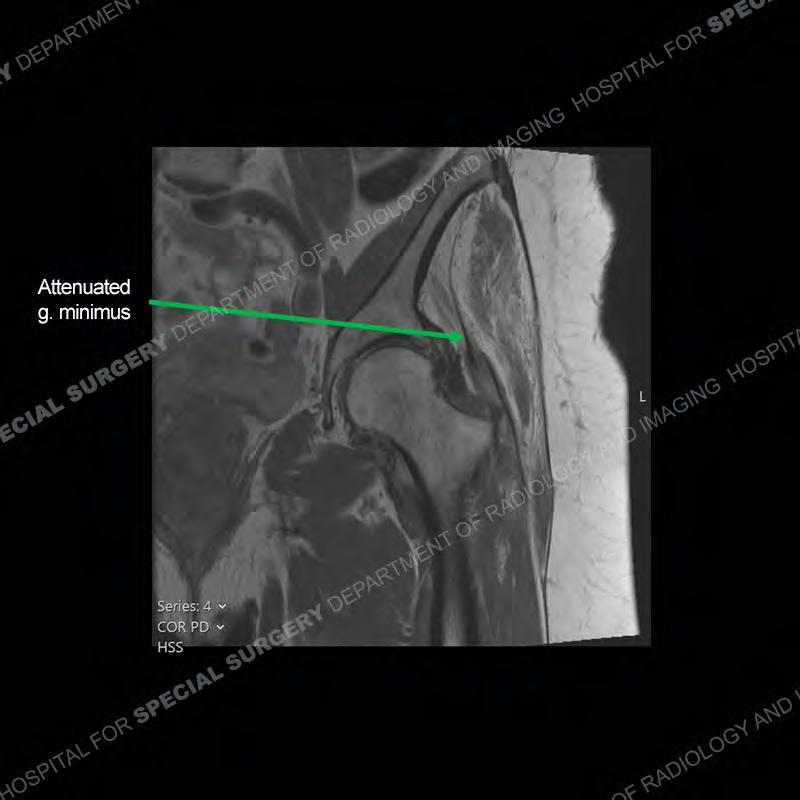

The radiograph is not particularly contributory in this case. The MRI demonstrates markedly abnormal architecture of the gluteus minimus and anterolateral band of the gluteus medius. Portions of the tendons are high signal, portions are highly attenuated, and portions are disrupted. A large, complex fluid collection is present in the adjacent soft tissue.

Not as much of a diagnostic dilemma as many of the other cases shown but just a nice example of the pathology seen of the gluteal tendons and a cause of trochanteric pain. Although, frequently thought of in isolation, trochanteric bursitis or bursal thickening is much more commonly a reactive change to underlying pathology of the subjacent gluteal tendons. The gluteus medius is divided into a posterior band and an anterolateral band. Tendinosis and partial tearing very commonly will involve the gluteus minimus and especially the more posterior fibers and then propagate into the anterior lateral band of the gluteus medius. Involvement of the posterior band of the medius is much less common and engenders a marked degree of functional impairment.